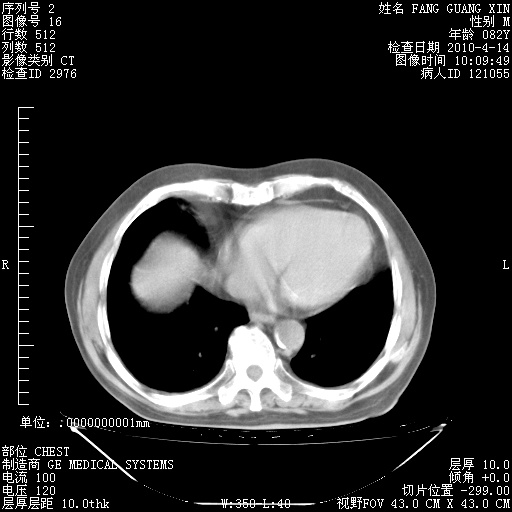

4月14日肺部CT

15.JPG

16.JPG

17.JPG

18.JPG

19.JPG

fgx.JPG